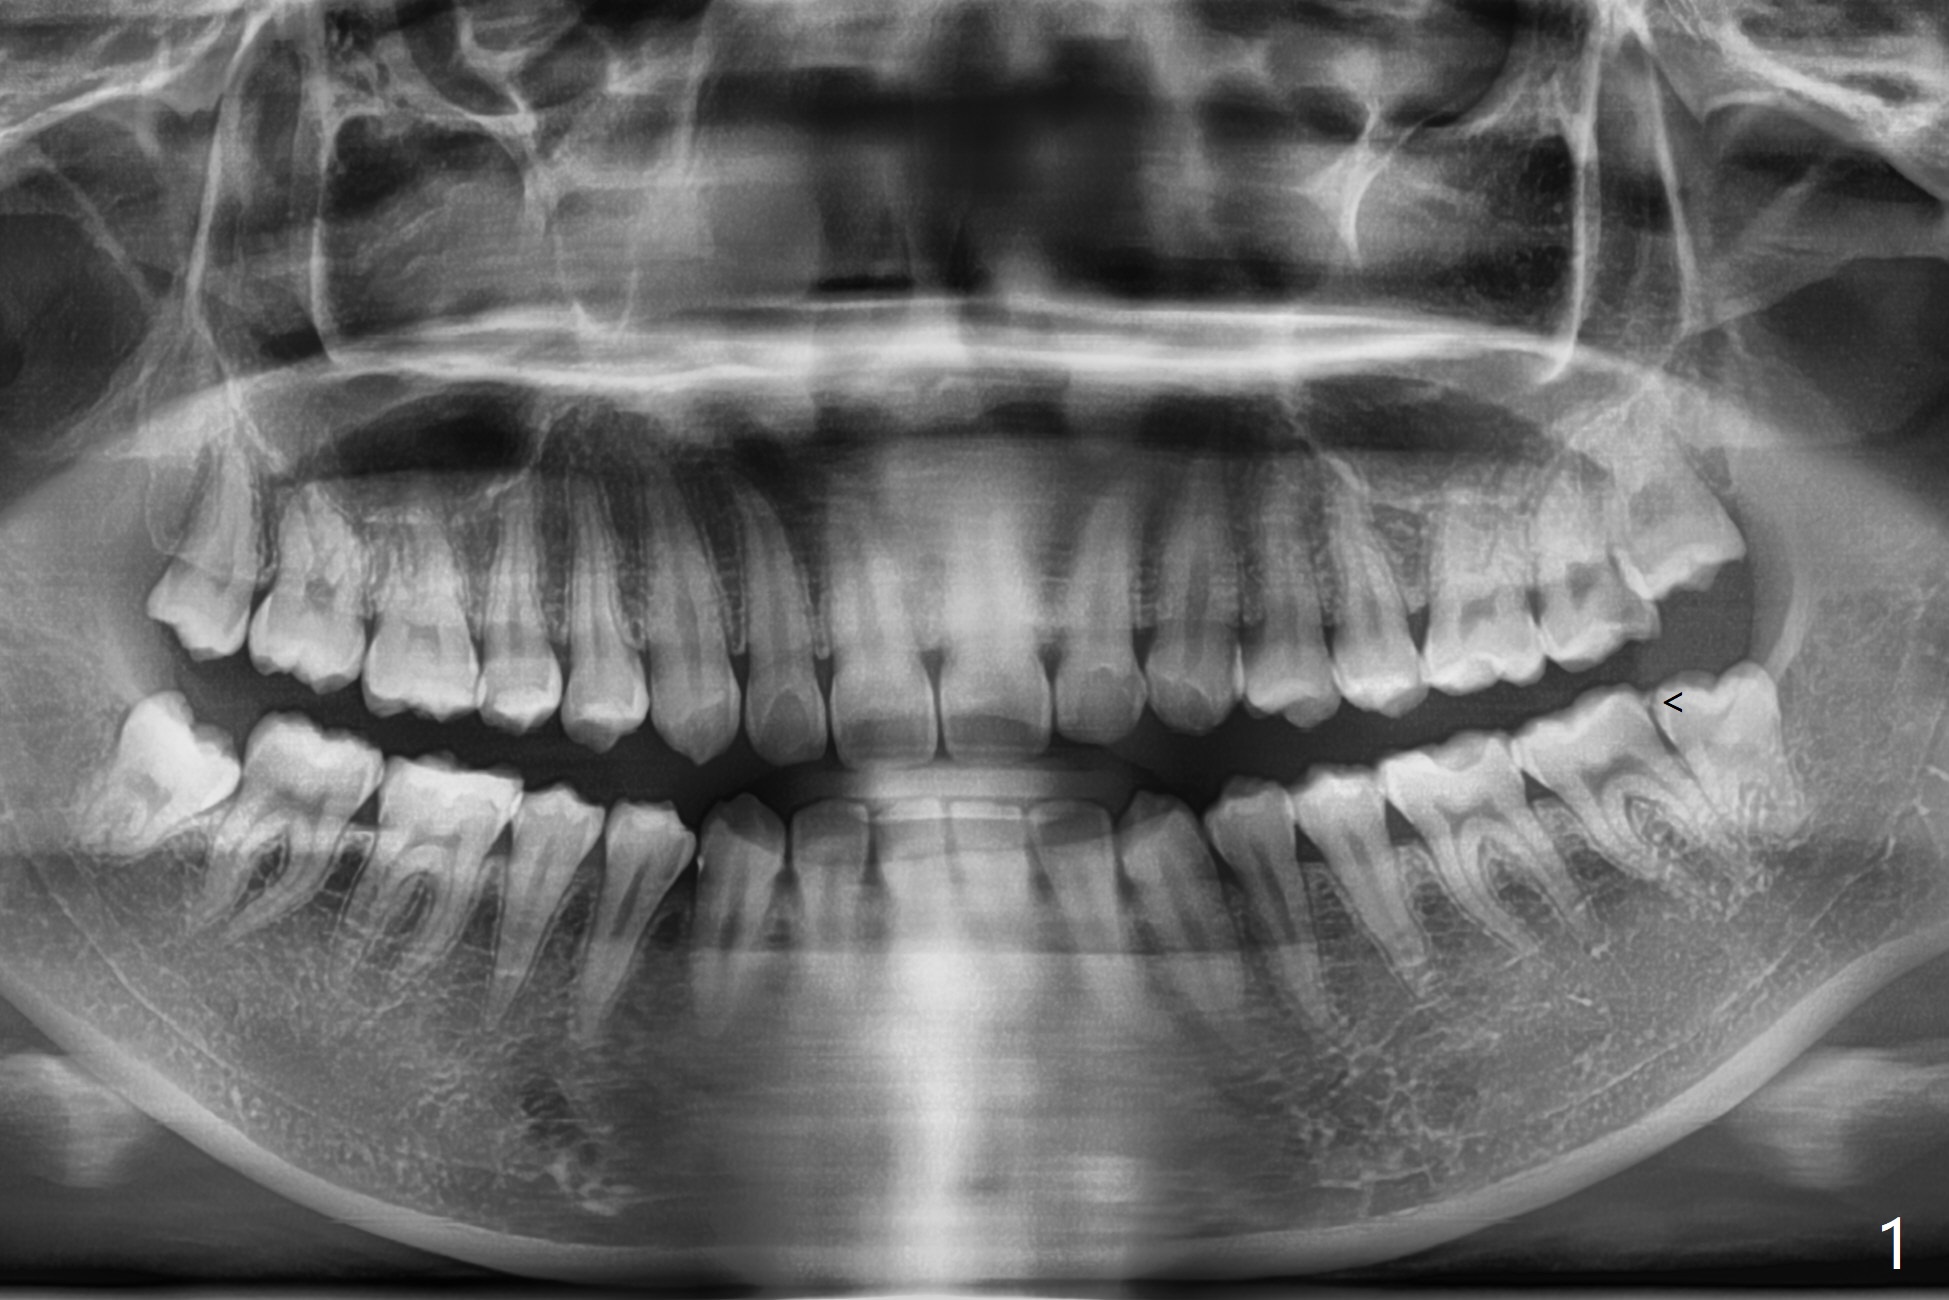

A 23-year-old woman requests #17 extraction because of pain as related to late night lactation (Fig.1 (food <)). The tooth is removed with buccal trough and sectioning (avoiding mesial elevation as much as possible). Osteogen plug is placed against the mesial wall of the socket (horizontal placement, Fig.2).